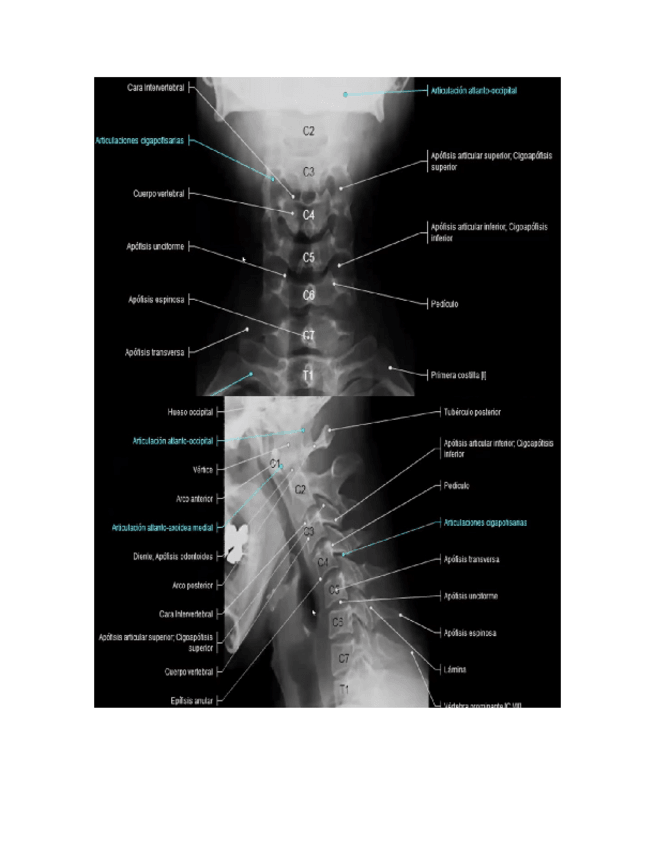

COLUMNA-VERTEBRAL-NORMAL.docx

RX-DE-COLUMNA-VERTEBRAL.pdf